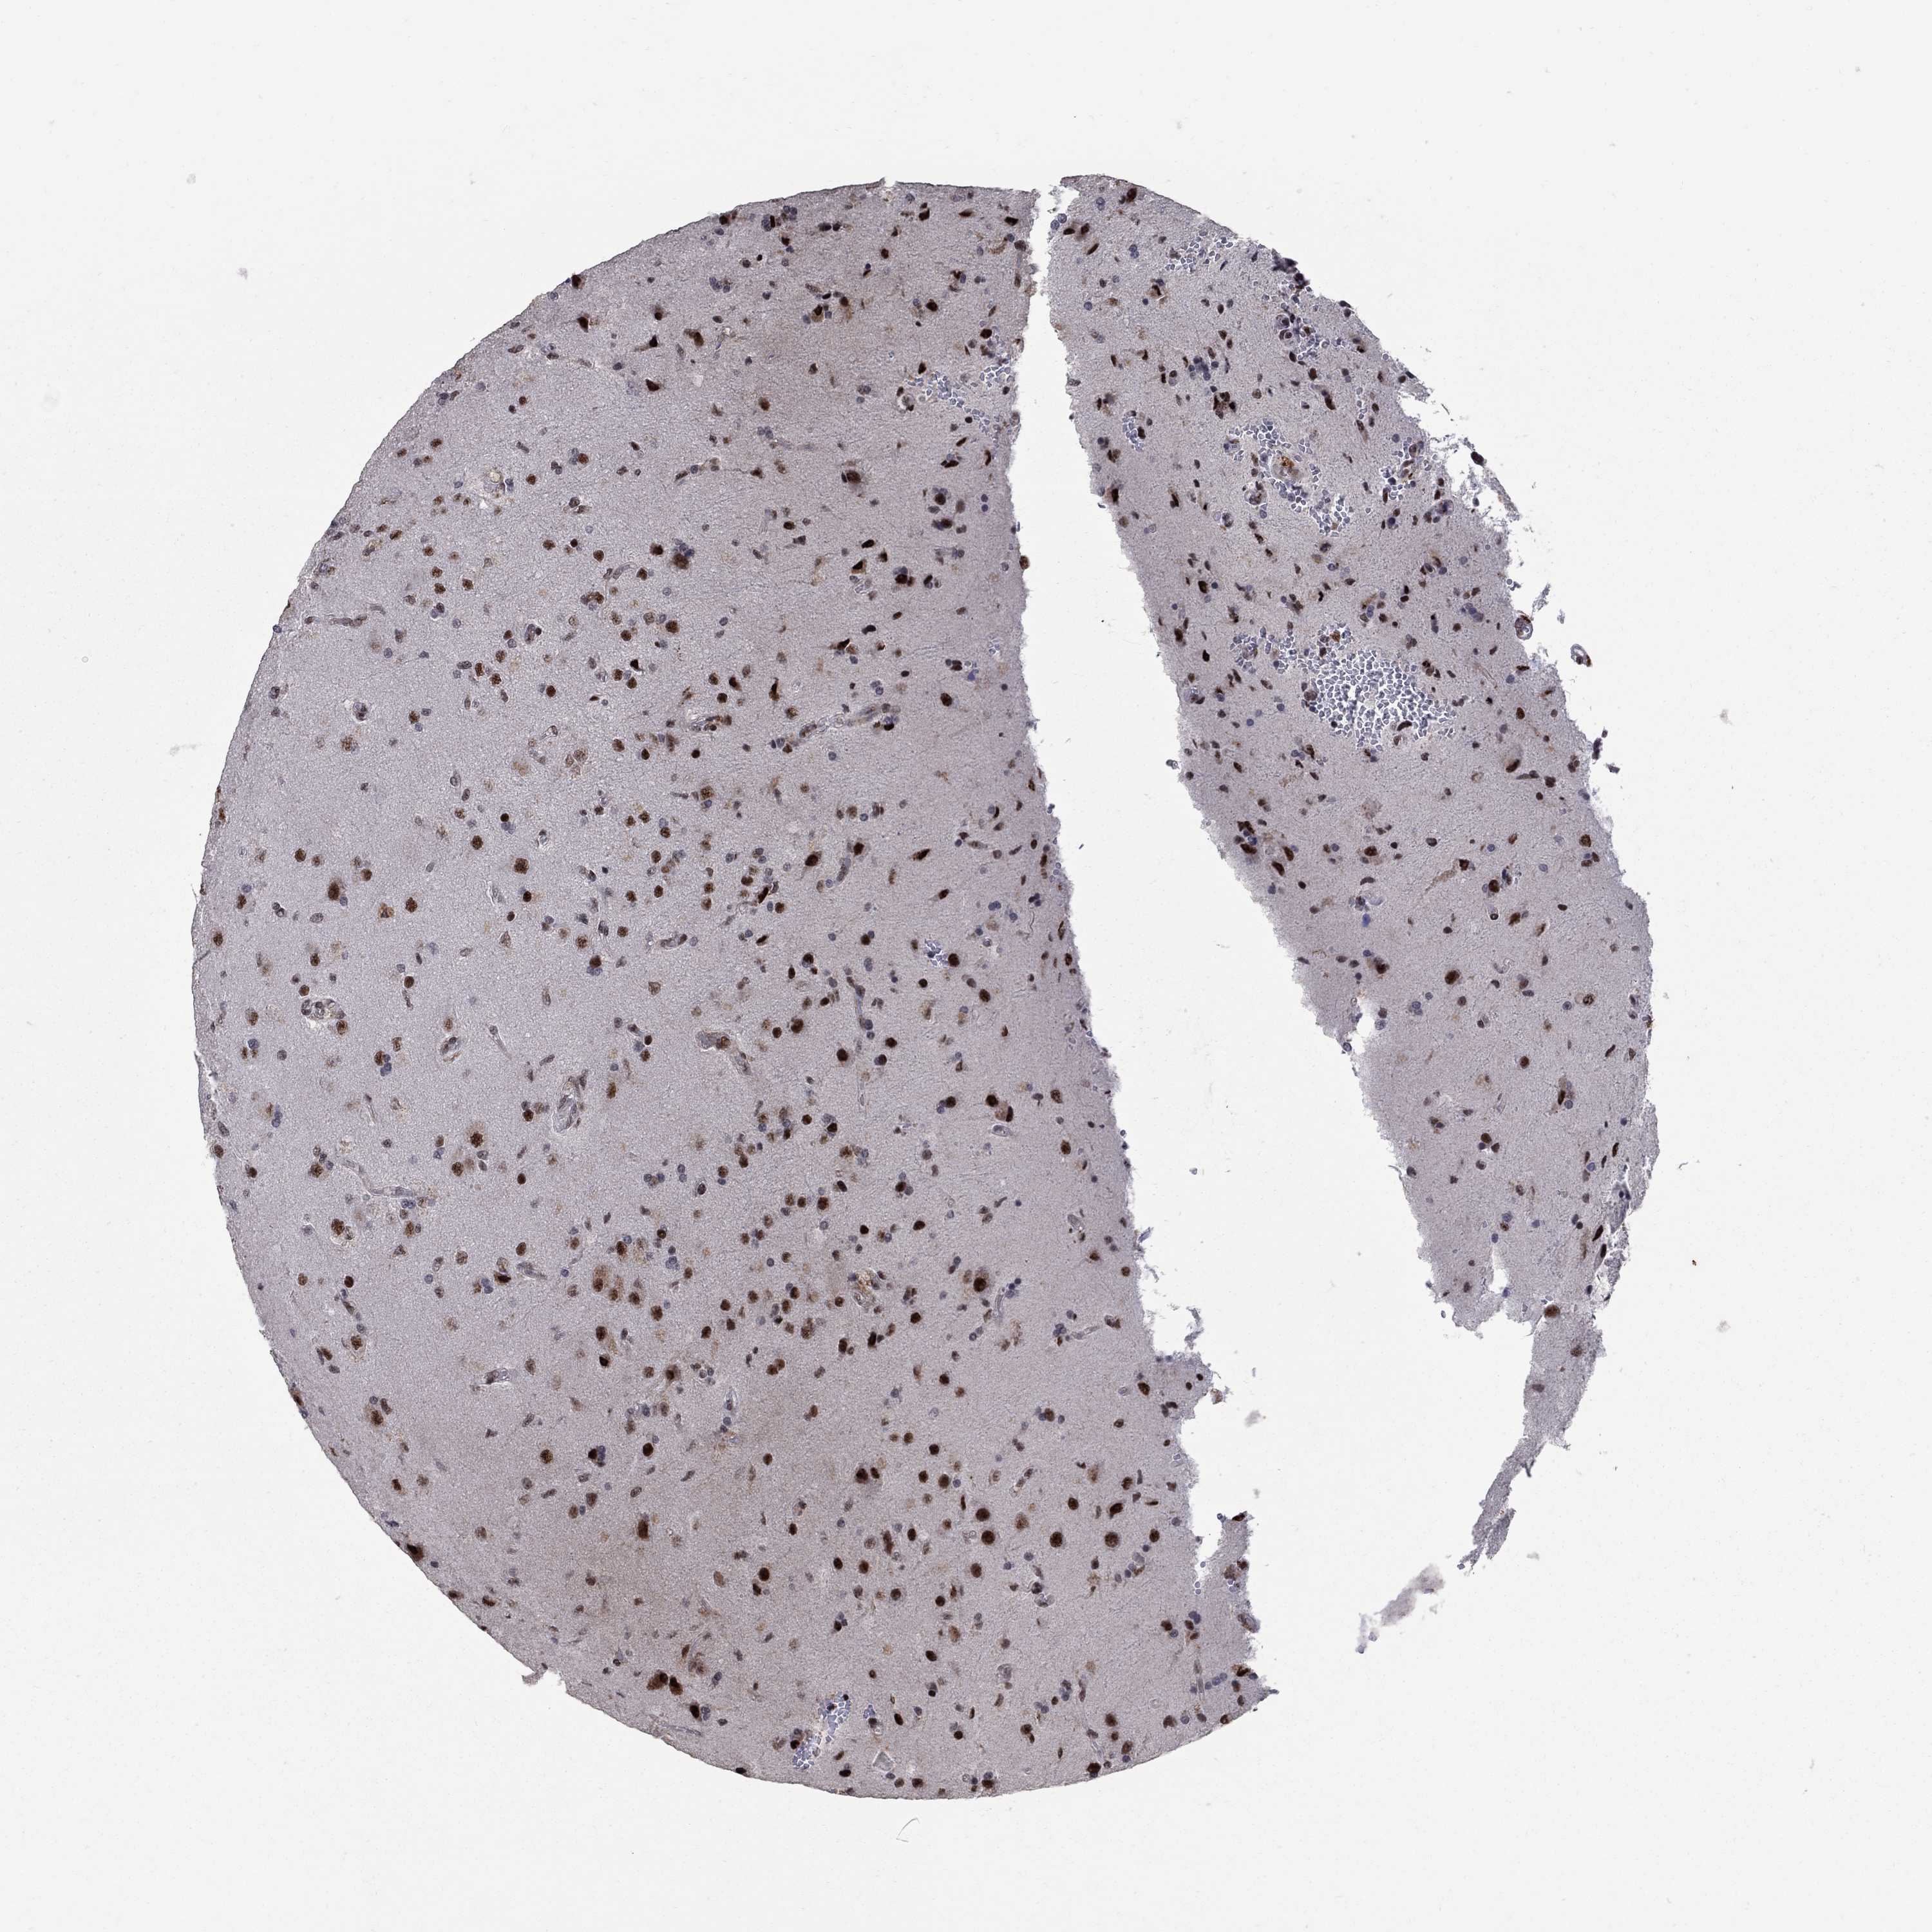

GLIOMA - Protein expressioni

A mouse-over function shows sample information and annotation data. Click on an image to view it in a full screen mode. Samples can be filtered based on level of antibody staining by selecting one or several of the following categories: high, medium, low and not detected. The assay and annotation is described here.

Note that samples used for immunohistochemistry by the Human Protein Atlas do not correspond to samples in the TCGA dataset.

Antibody stainingi

Antibody staining in the annotated cell types in the current human tissue is reported as not detected, low, medium, or high, based on conventional immunohistochemistry profiling in selected tissues. This score is based on the combination of the staining intensity and fraction of stained cells.

Each image is clickable and will lead to virtual microscopy that enables deeper exploration of all samples and also displays staining intensity scores, fraction scores and subcellular localization as well as patient and tissue information for each sample.

Antibody HPA075076

Staining

High

Medium

Low

Not detected

Intensity

Strong

Moderate

Weak

Negative

Quantity

>75%

75%-25%

<25%

None

Location

Nuclear

Cytoplasmic/membranous

Cytoplasmic/membranous,nuclear

Glioma, malignant, Low grade

Glioma, malignant, High grade

Glioma, malignant, NOS